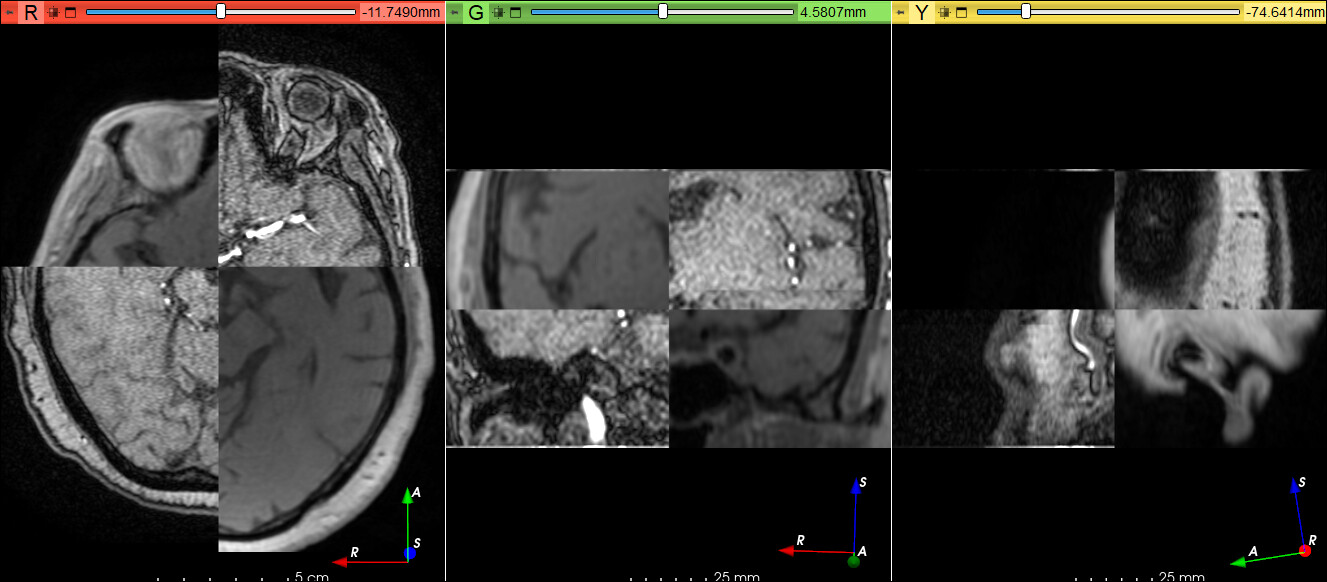

数据:培训数据2022\019配准练习数据\tof+T1

点击Add 分别在双侧眼球和四脑室放置3个基准点,注意配准

配准类型可以选择:

affine registration 仿射配准

plastimatch

thinplate registration

配准模式选择

Rigid 刚性

Similarity 相似

Affine 仿射